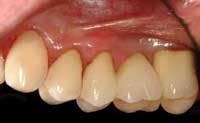

4) Determination of the patient's ability to get a loan for the services — Some patients with good credit ratings are willing to get a loan, pay the interest on it, and have the treatment performed as soon as possible. This is the ideal situation, but let's assume the patient cannot or will not get a loan. Such a patient is shown in Figs. 1, 2, and 3.

This amount of treatment may be more than the patient can afford in one year, even when using any third–party benefit that is present. If so, segment the first portion into more piecemeal treatment, doing only the mandatory therapy first. As an example, if a significant amount of therapy has been needed before treating the six anterior teeth, these teeth may be treated in the second year. However, I prefer treating the upper anterior teeth in the first year if possible. Often, the anterior teeth can be treated conservatively rather than using crowns, to provide even more motivation for the patient to continue with the therapy. (See Fig. 4.)